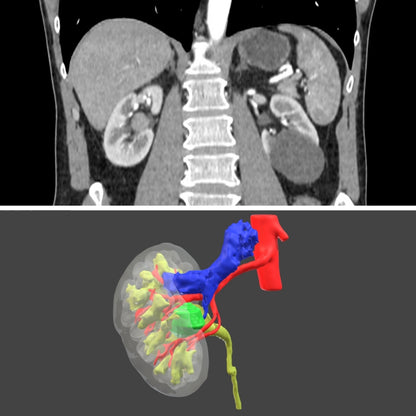

Surgical planning - Digital 3D model for urology

Surgical planning - digital model

Only for urology

Plan your next surgery with a 3D model of the patient's exact anatomy. This planning is done based on the CT scans.